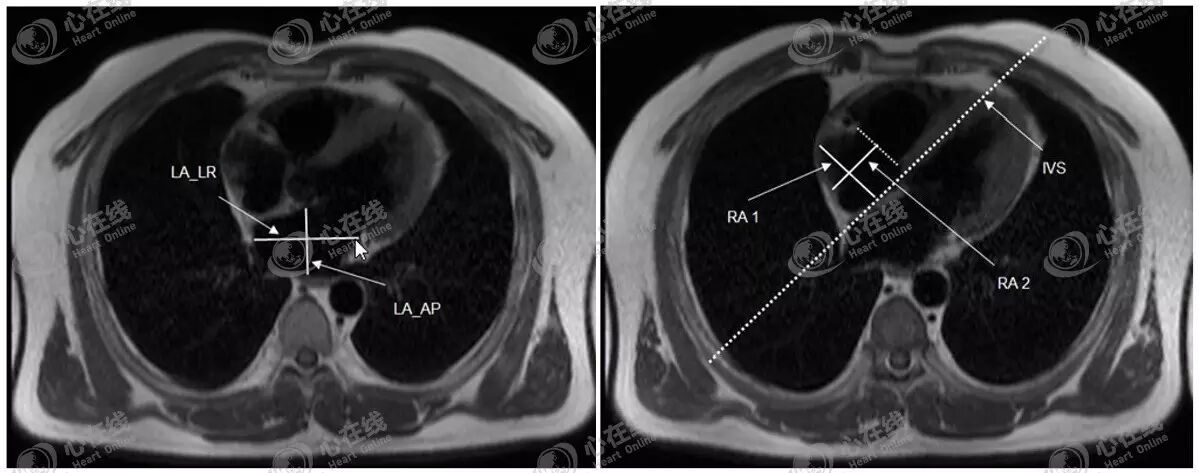

5、其他径线测量

左房一般是测量前后径,但在左房增大时,前后径扩张的空间有限,而常向左右扩大,因此可附加测量左房的左右径。如图11左图,经左房前后径(LA_AP)中点做垂直线,即可获得左房左右径(LA_LR)。

也可测量右房大小。如图11右图,选择右房显示最大时的平面,首先经三尖瓣口做一连线,,即为右房的左右径(RA1),然后经左右径中点做一垂直线,与三尖瓣口连线相交,即为右房的前后径(RA2)。

图11